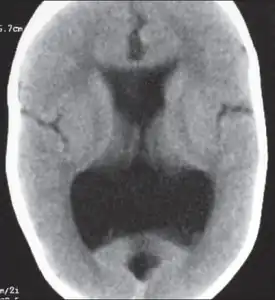

Colpocephaly is characterized by disproportionately large occipital horns of the lateral ventricles (also frontal and temporal ventricles in some cases). MRI and CT scans of patients demonstrate abnormally thick gray matter with thin poorly myelinated white matter. This happens as a result of partial or complete absence of the corpus callosum. Corpus callosum is the band of white matter connecting the two cerebral hemispheres. The corpus callosum plays an extremely important role in interhemispheric communication, thus lack of or absence of these neural fibers results in a number of disabilities.[12]

The lemon sign on CT scans of patients refers to the shape of the fetal skull when the frontal bones lose their normal convex contour and appear flattened or inwardly scalloped. This gives the skull a shape similar to that of a lemon. The sign is seen on transverse sonograms of the fetal cranium obtained at the level of the ventricles. A special case is found in literature where lissencephaly, colpocephaly, and septal agenesis are all present together. The CT scans of the patient shows the ventricular system having a unique appearance of a crown of a king. This is referred to as the 'CROWN SIGN'.[8]

Image indicates colpocephaly with septal agenesis

After birth, MR imaging can be done to look for cephalic abnormalities. This is the most commonly used method for diagnosing colpocephaly. Physicians look for abnormally large occipital horns of the lateral ventricles and diminished thickness of white matter.[12] Spinal tapping is not a preferred method for diagnosis because newborn babies with colpocephaly or hydrocephaly have open fontanelles which makes it difficult to collect CSF. Also, colpocephaly is not associated with increased pressure.[13]